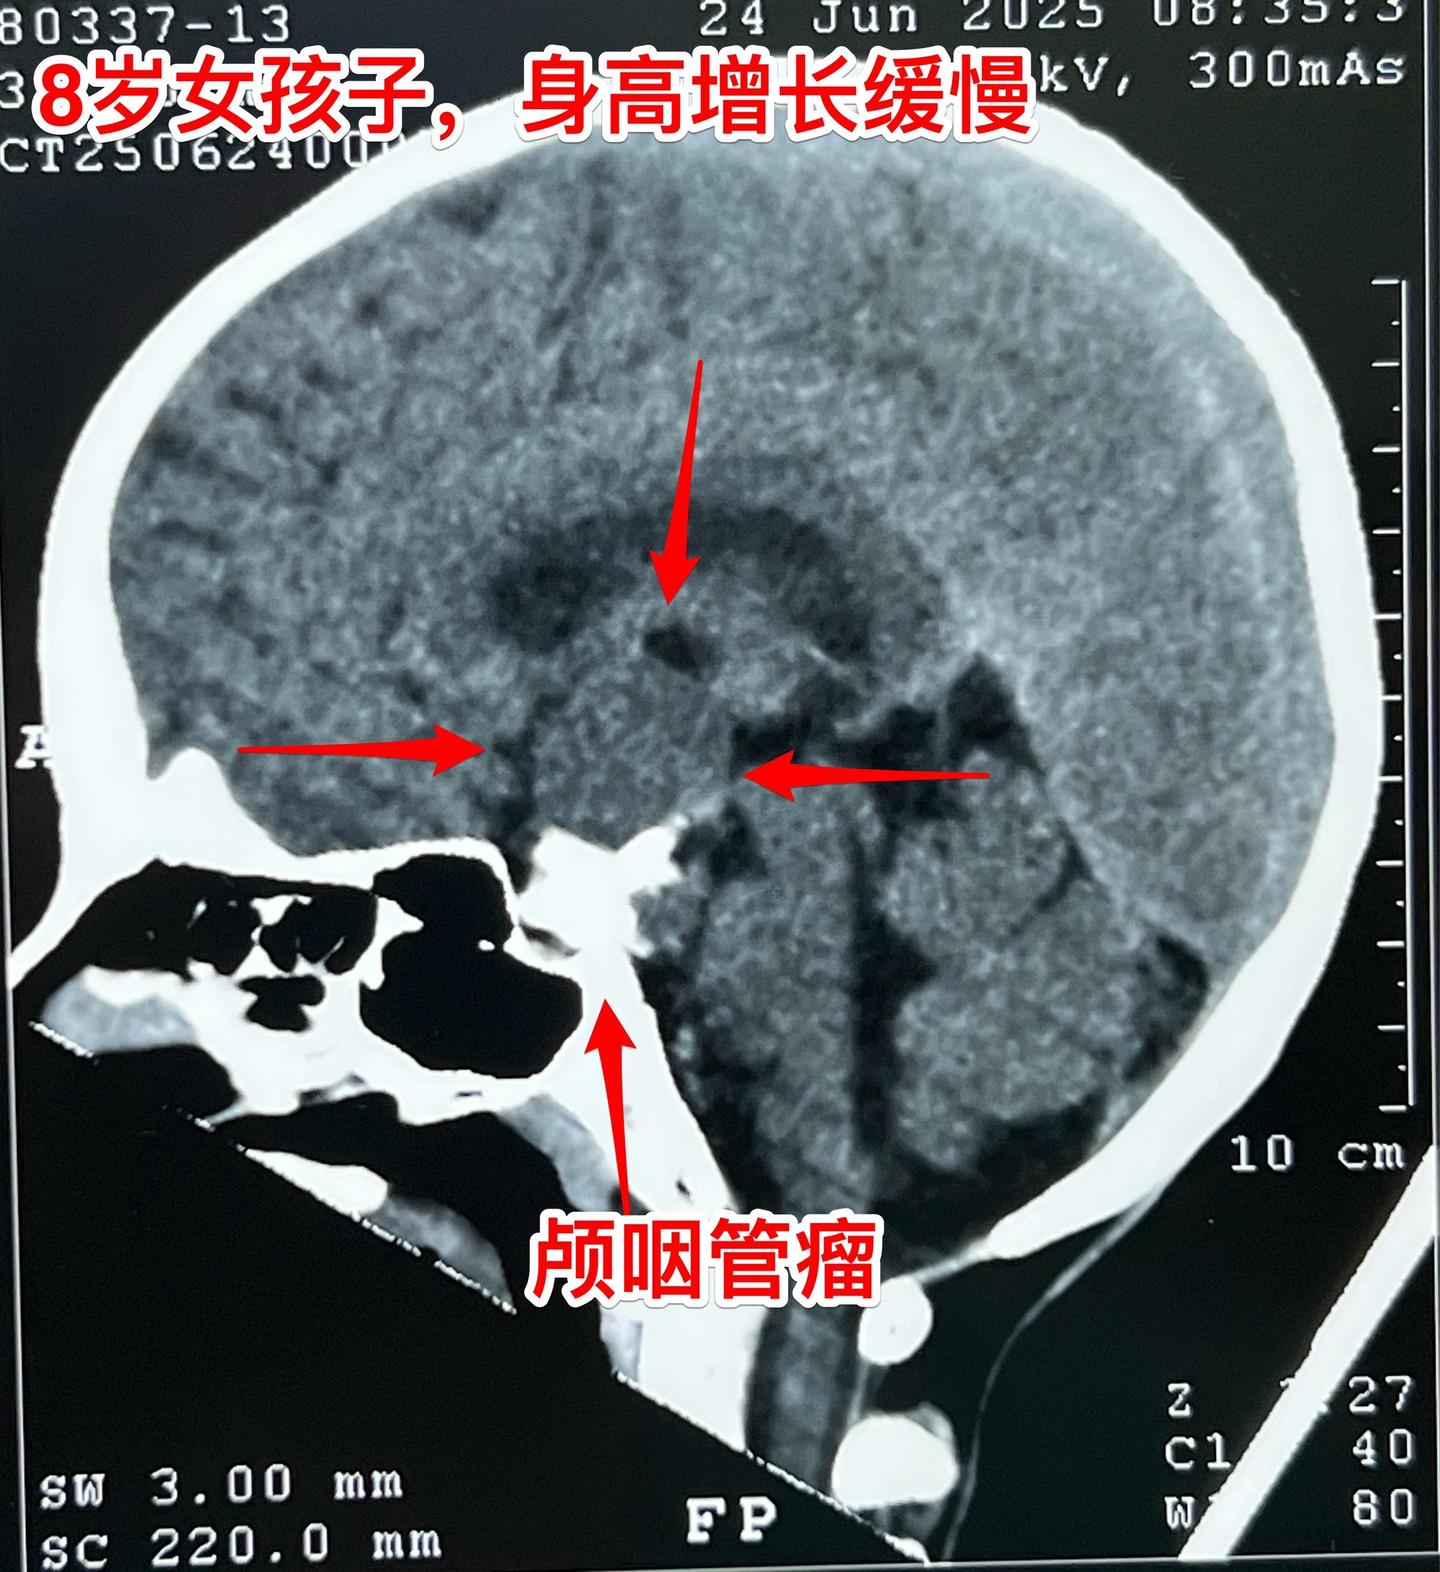

八岁烟台女孩子身高增长缓慢—原因找到了。八岁女孩子,父母都是大高个。近两年女孩子身高增长很缓慢,一开始没有引起重视。随着身高差距拉大,家长重视起来了。 2025年6月到医院检查头部磁共振、CT,一下子就找到原因了:脑部长了颅咽管瘤,这个颅咽管瘤还有一大块钙化。 女孩子除了身高增长缓慢之外,无视力下降,无多饮多尿症状,精神状态也很好。 女孩子的舅舅也是神经外科医生,上周找我看了门诊,他们接受开颅手术。 今天的手术很顺利,颅咽管瘤得到完全切除。